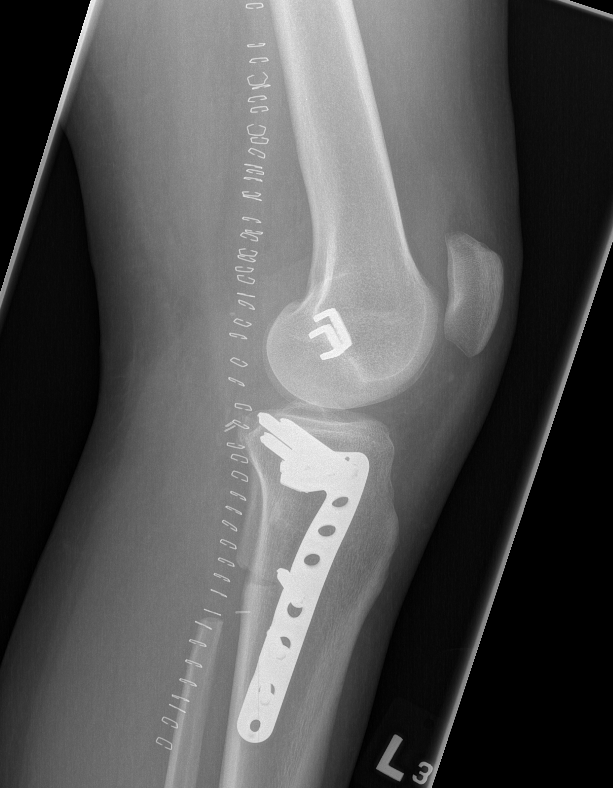

Technique

Cortical window

- burr / currette

- phenol / cryotherapy / liquid nitrogen